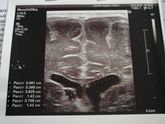

Нам 8 месяцев... Не много но уже и не мало... Сын совсем большой уже ребёнок который все осознает понимает! Видно уже характер очень упертый это наверное в меня ?пока свое не получит не успокоится ?кушаем все овощи, фрукты, каши, кефир, компот... Весим … Читать далее